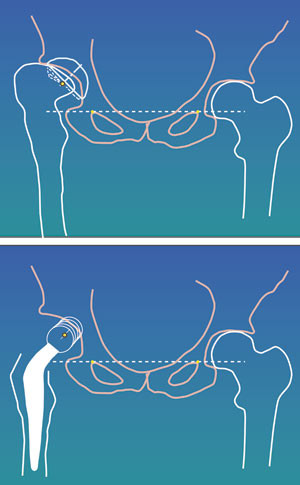

Vi har et nært samarbeid med miljøet i Trondheim. Røntgenavdelingen i Arendal gjør en tredimensjonal CT-fremstilling av pasientens øvre femur, dataene blir sendt elektronisk til Trondheim, og femurkomponenten fremstilles deretter i en datastyrt produksjonsprosess (fig 1). Protesen er laget av titan. Det tilstrebes at protesen har optimal kontakt til 1,5 – 2 cm nedenfor trochanter minor, det samme område er belagt med hydroksyapatitt på en porøs overflate (fig 2). Collumanteversjonen er standardisert til 10°. Operatøren får tilsendt operasjonsdokumentasjon fra produsenten. Det er ut fra femurkomponentens halslengde og halsvinkel at operatøren kan velge medial offset, fremre offset (fig 3) og bestemme ønsket beinlengde (fig 4). Deretter ferdigstilles den individtilpassede hofteprotesen. Det følger med en reseksjonsmal for collumkuttet, og instruksjon om hvordan malen skal stilles inn for den enkelte pasient. Det følger også med 1 – 2 spesialtilpassede rasper for preparering av femurkanalen (fig 5). Kun femurprotesen er individtilpasset, for acetabulum benyttes standard acetabularproteser.

Harris’ hofteskår ble målt preoperativt og postoperativt etter ett år. Gjennomsnittlig skår preoperativt var 49 (spredning 27 – 66) og postoperativt 97 (spredning 76 – 100). Preoperativt var det aktuelle bein kortere (1 – 3 cm) hos 20 pasienter. Postoperativt var beina like lange hos 35 pasienter, hos én pasient var beinet fortsatt 1 cm for kort, og hos én pasient var beinet blitt 1 cm for langt (overkorreksjon). Eksempler på bruk av den individtilpassede hofteprotesen fremgår av figur 6, figur 7 og e-figur 8.